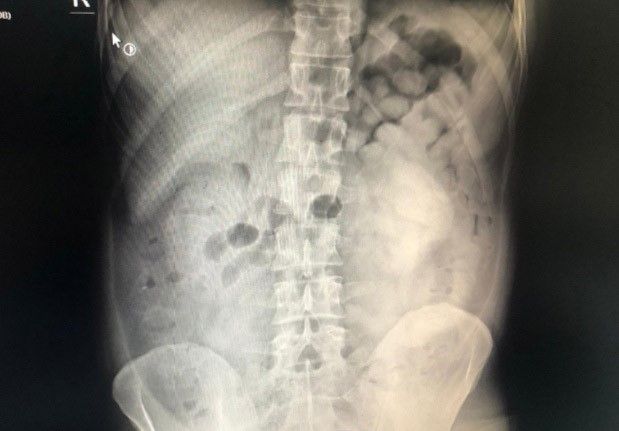

Doktor muayenesi ve çekilen film sonucunda şüphelinin sindirim sisteminde 800 gram eroin maddesi ele tespit edildi.